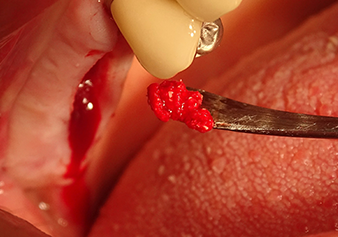

Following an intermediate check (Fig. 4) a further preparation step was performed (Fig. 5). Afterwards, the hydraulic Z35P instrument was used to lift the membrane to the desired position (Fig. 6 and 7). This was followed by further piezosurgical preparation of the implant bed, concluded with a rotary bur and shoulder milling cutter up to the implant diameter of 4.8 mm. Before the implant was inserted, the augmentation material (particle size approx. 0.8-1.6 mm) was introduced underneath the Schneiderian membrane (Fig. 8).

Implantation and prosthetic restoration

To move the augmentation material in the direction of the maxillary sinus atraumatically, the implant was inserted very slowly by hand (Fig. 9). In the process, the membrane was pushed in the cranial direction once again. After two months, the surgical site healed without irritation. Six months later, the x-ray check showed a significant increase in opacity as an indication of ossification (Fig. 10). The prosthetic restoration was carried out with a metal-ceramic crown.